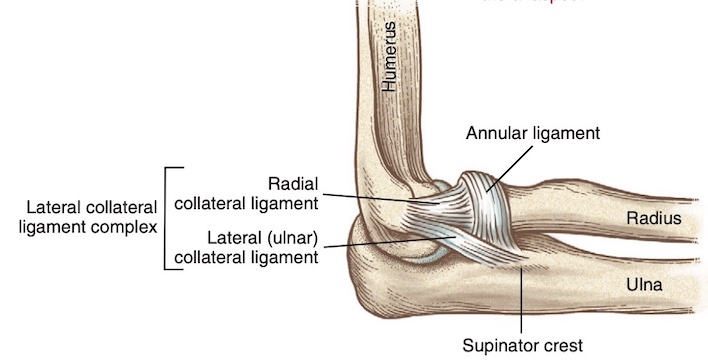

- Phức hợp dây chằng bên ngoài bao gồm dây chằng bên quay, dây chằng vòng quay (annular ligament), và dây chằng bên trụ ngoài (lateral ulnar collateral ligament). Dây chằng bên trụ ngoài đóng góp nhiều nhất vào sự ổn định ở mặt ngoài của khớp khuỷu. Tổn thương cấu trúc này có thể dẫn đến mất vững xoay sau ngoài.

- Dây chằng bên quay làm vững bên ngoài và ít khi bị chấn thương.

- Dây chằng vòng quay ôm quanh chỏm xương quay để giữ vững.